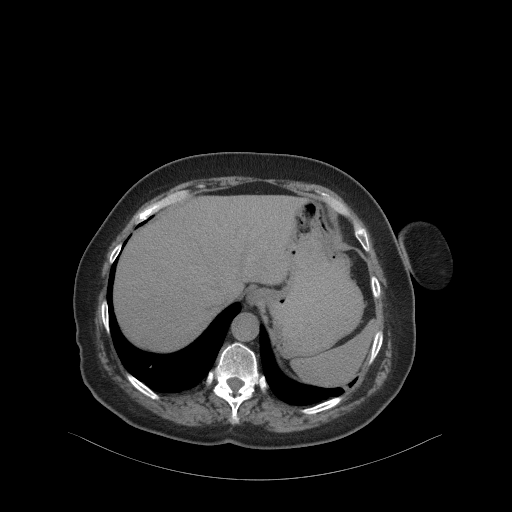

Original NATIVE CT scan (input)

Full window (WL 1023.5, WW 4095 β†’ Low βˆ’1024, High +3071)

Actual HU range: [-160.0, 240.0]